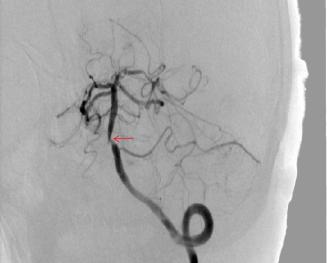

脑血管造影:

最后终于诊断出:椎基底动脉TIA、基底动脉狭窄、右侧大脑中动脉狭窄。

治疗:患者拒绝血管内介入治疗,经阿司匹林+氯吡格雷双联抗血小板聚集、阿托伐他汀强化调脂等治疗后患者未出现短暂性意识丧失发作。

理想情况下,对于椎基底动脉短暂性脑缺血发作的患者均应进行卒中单元治疗,反复出现意识丧失,还应进行ICU治疗。MRI较CT对缺血更为敏感,DWI更可发现急性期病灶,DSA是明确血管情况金标准。